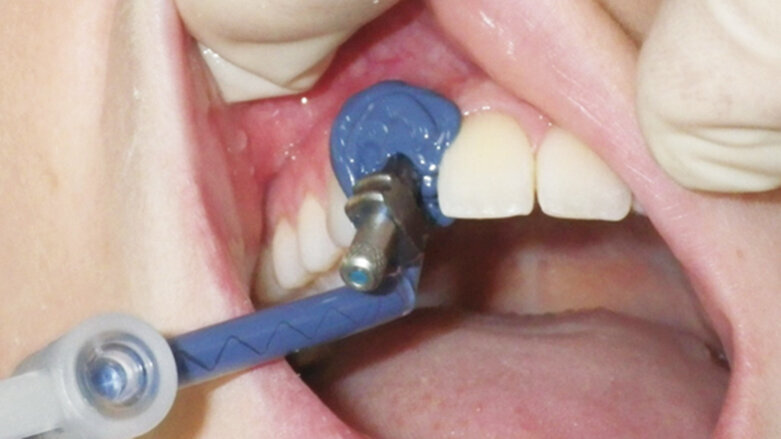

A marking medium was placed on the top surface of the implant impression screw and this marking was transferred to the inside of the tray by seating the tray intraorally (Fig. 3). An acrylic bur was used to create a hole in the base of the tray (Fig. 4) and the impression tray was then tried in the mouth to ensure that there was clear access to the impression screw (Fig. 5).

Fig. 4. An acrylic bur is being used to cut a hole in the tray to access the impression screw.